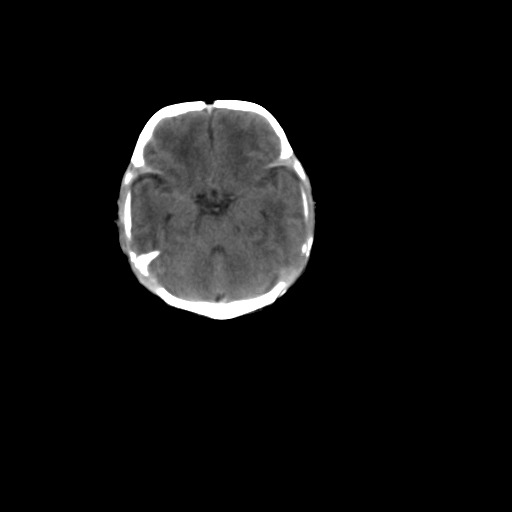

男,12天,自然分娩,其母发现右顶部头皮包块逐渐增大。

右顶骨呈膨胀性改变,骨纤维结构不良?

疑问:患儿脑白质密度比较低,基底节区密度比较高,类似于“双圈征”脑沟密度也偏高。该婴儿可有别的异常吗?反射正常吗?评分能达到5分吗?如果正常,就随诊观察吧。不正常要考虑到缺血缺氧性脑病。